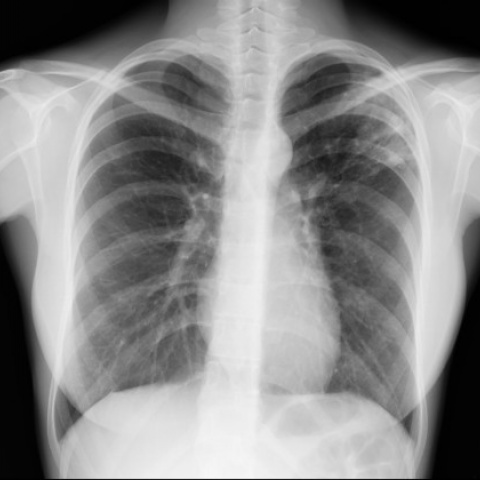

Aplicația tânărului se bazează pe doi algoritmi care pot citi radiografia pe loc: "Rezultatul apare aproape instant.

Pe această radiografie puteţi observa o leziune destul de mare. Algoritmul ne indică mai multe probleme printre care tuberculoza. Utilitatea cea mai mare va fi în gărzi pentru că volumul de investigaţii e din ce în ce mai mare".